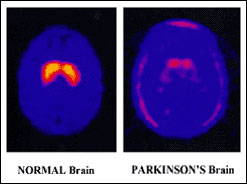

|  |  | | Parkinson's Disease

Barbara Myers is back with a new series of Check Up, the health phone-in, where you put your questions direct to the experts. In the first programme, Barbara and her guest will be answering your queries on Parkinson’s Disease. Parkinson’s is a progressive neurological condition affecting movements such as walking, talking and writing. It is named after Dr James Parkinson (1755-1824), the London doctor who first identified Parkinson’s as a specific condition.

In the UK, one in 500 people, or around 120,000 individuals have Parkinson’s. Usually symptoms appear after the age of 50 and the risk of getting Parkinson’s increases with age. Parkinson’s has three main symptoms - tremor, muscular stiffness that can affect posture and forming facial expressions, and a slowing of movement.